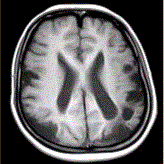

问题 女性,22岁。癫痫发作及智力异常。MRI显示见下图。 有关该病的描述,正确的是

选项 A.多种原因引起颅底大动脉严重狭窄或闭锁,并可见脑底部代偿性异常血管网 B.MRT2WI显示基底节区多发点状血管流空信号 C.DSA显示willis环闭塞,颅底区烟雾状侧支循环 D.CT显示低密度病灶,为缺血、梗死所致,特征是双侧性和多发性 E.影像学首选MRA及MRI F.主要发生在老年人 G.多见于颈内动脉床突上段和大脑前、中动脉近段和基底动脉远端

答案 ABCDEG